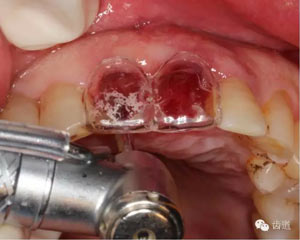

微創(chuàng)拔除根折牙

拔牙窩

探查唇側(cè)骨板(約齦下3-4mm)